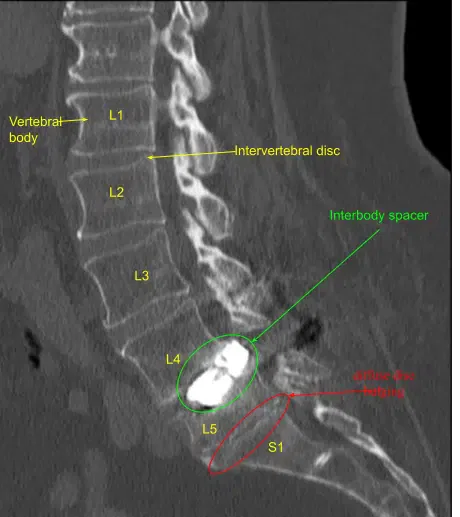

Se realizó una tomografía computarizada intraoperatoria. Los datos se transfirieron al ordenador de neuronavegación. Se verificó la exactitud. Se utilizaron técnicas estereotácticas de neuronavegación guiadas por imagen para reposicionar y reemplazar el nuevo tornillo pedicular en L4, en el lado derecho, en la posición adecuada.

A continuación, se realizó un TAC intraoperatorio que mostró la posición correcta de todos los tornillos. A continuación, realizamos una laminectomía L3-4 utilizando rongeurs de Leksell que recogieron autoinjertos para morselización en caso de artrodesis, exponiendo un ligamento flavo hipertrófico que fue retraído de forma fragmentada con rongeurs de Kerrison.

Los espacios intersombólicos se irrigaron hasta despejarlos, repletos con autoinjertos fragmentados de la descompresión, así como con aloinjerto de matriz ósea desmineralizada, y luego se colocó un espaciador intersomal de titanio expandible bajo guía fluoroscópica estéril en vistas AP y laterales hasta colocarlas correctamente. Las señales de neuromonitorización se mantuvieron estables. La neurolisis bilateral de L3-4 se realizó con la técnica de Metzenbaum-Penfield y se confirmó con un gancho nervioso circunferencialmente.